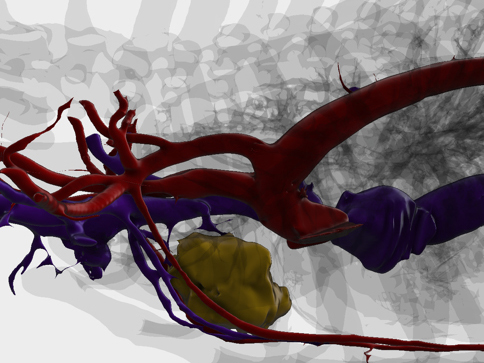

CT検査のデータを3D画像化し血管走行等を把握